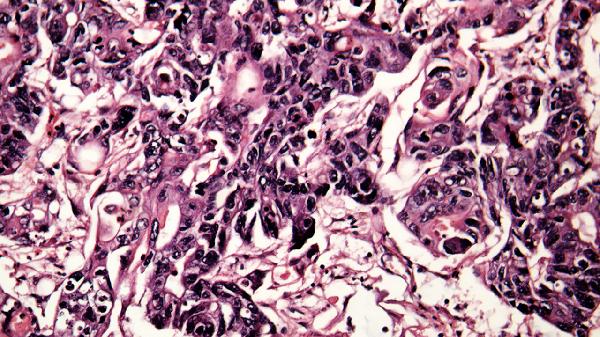

细菌感染通常是由病原菌通过呼吸道、消化道或皮肤伤口进入体内引起的。比如,宝宝可能通过触摸不干净的玩具、餐具,或者吸入空气中的细菌而感染。常见的细菌感染包括呼吸道感染、肠胃炎、皮肤感染等。这些感染可能表现为发烧、咳嗽、腹泻、皮疹等症状,需要家长及时关注。